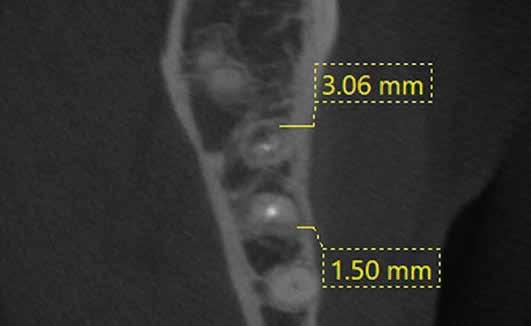

a-m. ábrák: Preoperatív röntgenfelvétel (a) és preoperatív CBCT-felvétel a jobb felső 5-ös (1.5) fogról, sagittalis (b) és axialis (c) nézetek. Az intraorális szkennelés során kapott STL-fájl (d). A 1.5-ös fog navigált endodonciai mikrosebészeti beavatkozásához tervezett sablon (e). A 1.5-ös fog navigált endodonciai mikrosebészeti beavatkozásához nyomtatott sablon (f). Teljes vastagságú mucoperiostealis lebenyt emeltünk (g). A sablont a helyére illesztettük, és a csontablak határait jelöltük (h). A fog gyökerén kívül eső, betört eszköz a 1.5-ös fog periapicalis régiójában (i). Az eltávolított betört eszköz (j). A rezekció, retrográd preparáció és a TotalFill BC RRM Fast Set Putty anyaggal elkészített retrográd gyökértömés utáni röntgenfelvétel (k). A lebenyt varratokkal rögzítettük (l). A kétéves kontroll során készített röntgenfelvétel (m).

Egy 38 éves nőbeteg a korábban kezelt jobb felső második kisőrlőfogából (1.5) kiinduló mérsékelt fájdalom miatt jelentkezett rendelésünkön. A kórtörténetében jelen panasza szempontjából releváns információ nem szerepelt. A beteg a klinikai vizsgálat során vertikális kopogtatásra enyhe érzékenységet jelzett. A kérdéses fog körül mérhető szondázási mélység és a fogmobilitás fiziológiás volt. Periapicalis röntgenfelvételen egy, a fog gyökércsúcsán túl presszálódott betört gyökérkezelő műszerből származó eszközfragmentumot láttunk (2. a. ábra). A preoperatív CBCT-felvétel a buccalis csontlemez épségét igazolta (2. b-c. ábra). A fog revíziója öt hónappal korábban történt. A már előzőleg gyökérkezelt, gyökértömött, majd revideált 1.5-ös fog esetében a diagnózisunk periodontitis periapicalis symptomatica volt. A periapikális elváltozás kezelése érdekében navigált endodonciai mikrosebészeti beavatkozást végeztünk.

A felső állcsontról intraorális szkent (TRIOS) készítettünk, és az ezáltal kapott STL fájlt (2. d. ábra) a CBCT-felvétel során nyert DICOM fájlokkal a Zirkonzahn.Implant-Planner (Zirkonzahn) szoftverben egyesítettük. A sebészi sablont ebben a programban megterveztük, majd a Meshmixer (Autodesk) szoftver se-

gítségével tovább módosítottuk. Az így kapott sebészi sablon egyértelműen meghatározta a periapikális terület eléréséhez szükséges csontablak határait (2. e-f. ábra) Helyi érzéstelenítést követően teljes vastagságú mucoperiostealis lebenyt képeztünk, majd a buccalis csont feltárását követően (2. g. ábra) a sablon segítségével bejelöltük a preparálandó csontablak határait (2. h. ábra). A csontablak kialakítása során Piezotome CUBE LED kézi-darabot alkalmaztunk, majd a leemelését követően a betört eszközt megkerestük (2. i. ábra) és eltávolítottuk (2. j. ábra). A rezekciót ultrahangos megmunkáló fejekkel (ACTEON) végeztük, majd retrográd preparáció következett.

A retrográd gyökértömés elkészítése során TotalFill BC RRM Fast Set Putty-t (FKG) használtunk (2. k. ábra). A lebeny széleit 5/0-s Prolene varratokkal egyesítettük (2. l. ábra). A varratok a műtétet követően 72 órával kerültek eltávolításra. A beteg két évvel később kontrollröntgen készítése céljából érkezett rendelőnkbe. A vizsgálat során a fog tünetmentesnek és funkcióképesnek bizonyult (2. m. ábra).